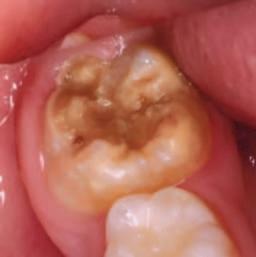

1. What condition is affecting the first permanent molar in Figure 1?

FIGURE 1: What condition is affecting this first permanent molar?